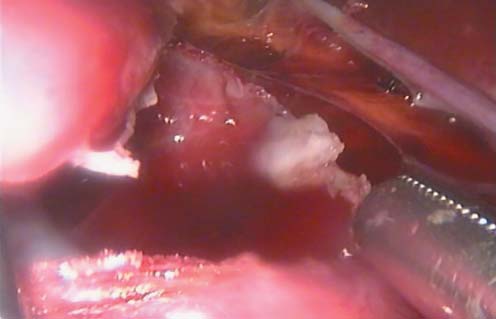

Киста вскрыта острым путем, произведена ревизия полости кисты - опухолевых элементов не

выявлено. С помощью аппарата биполярной коагуляции “Enseal" внепочечная часть кисты иссечена (рис. 4, 5). Стенка кисты удалена через один из 5 мм троакаров. Также через 5 мм троакар установлен дренаж к верхнему сегменту почки.

Рис. 4. Иссечение стенок кисты